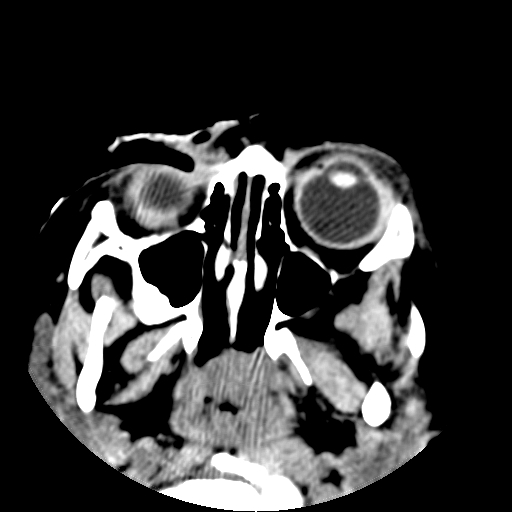

以下是引用深泽交通医院在2009-10-16 8:25:00的发言:[br]右眼环出血伴异物

以下是引用卜一在2009-10-16 15:01:00的发言:[br]右眼球挫裂伤伴异物!

以下是引用拾荒者在2009-10-17 18:38:00的发言:[br]鼻面部皮下积气,右侧睑缘及眼球壁高密度异物影,左侧眼球壁晶状体内侧缘处是圆形低密度影。低密度异物?应提请眼科医生注意。